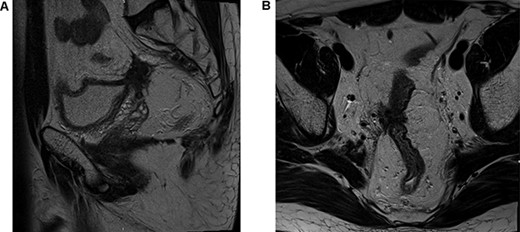

The patient underwent a defunctioning ileostomy at diagnosis. He completed 6 cycles of modified chemotherapy regime `FOLFIRINOX' (Folinic acid, fluorouracil, irinotecan and oaxliplatin) tolerated reasonably well, ECOG 0-1. He received Neulasta injections to prevent neutropenia during chemotherapy. This was followed by long course chemoradiotherapy (Capecitabine 825 mg/mtr2 twice daily, 5 days per week during radiotherapy). Repeat imaging 6 weeks post TNT demonstrated excellent response, reduction in bulky tumor previously noted on peritoneal reflection and bladder and extensive low signal scarring between rectum, peritoneal reflection, bladder and right sided internal iliac vessels (Fig. 2).

Post total neoadjuvant therapy (A) axial view and (B) sagittal view.